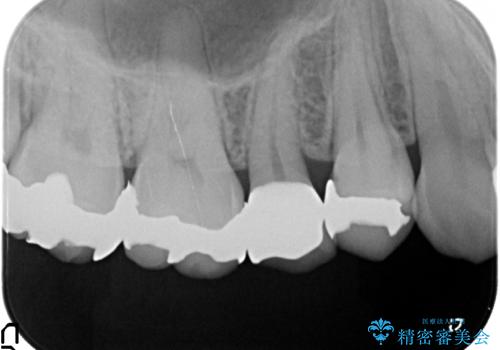

- 頬側から見たとき右上5番目の銀歯が気になるので、オールセラミッククラウンによる補綴を行った症例です。

今回用いたオールセラミッククラウンはジルコニアフレームという白い素材の上にセラミックを盛っているため、審美性が非常に高いのが特徴です。

また、ジルコニアは人工ダイヤモンドの材料にも使われているほど高い強度を持っており、そのためオールセラミッククラウンは審美性だけでなく、奥歯やブリッジの補綴も可能とするクラウンです。